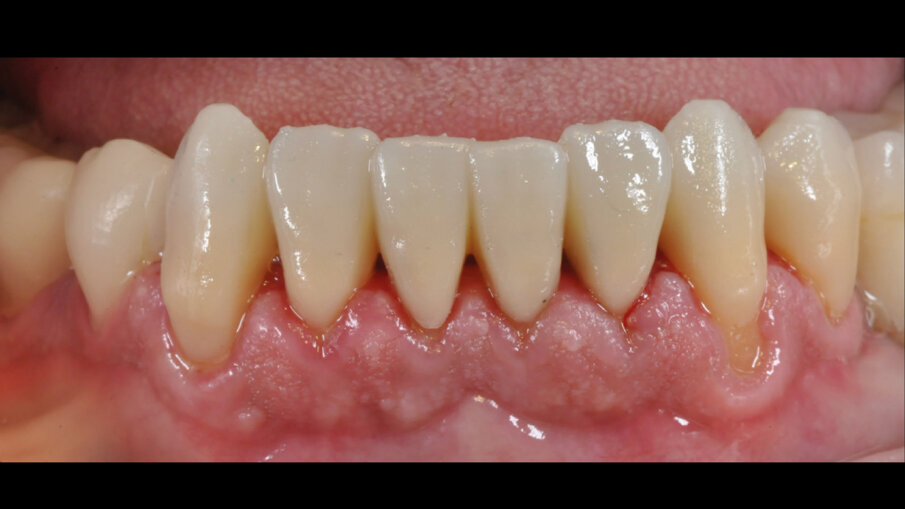

Fig. 1_Foto frontale delle arcate: situazione prima visita.

Il paziente è seguito regolarmente con controlli semestrali e sedute di igiene per mantenere la salute orale ed evitare carie secondaria e problemi parodontali. Manifesta piena soddisfazione per il trattamento ricevuto e rimane collaborativo. Nell’ultima visita, i restauri in composito ibrido Irix si presentano integri e funzionali. È necessaria solo una nuova lucidatura, eseguita dopo la seduta di igiene orale con la tecnica di lucidatura moderna appena descritta. Il paziente sarà monitorato e prevediamo di documentare il follow-up a medio e lungo termine (Fig. 7).